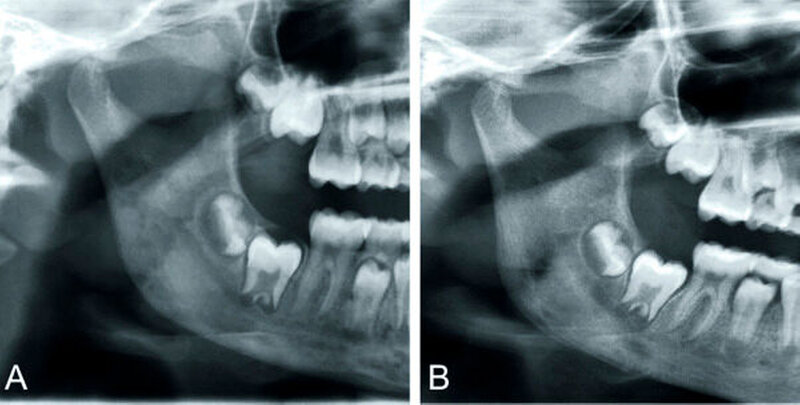

Die konventionelle Panoramaschichtaufnahme (PSA) hat als Ausgangsuntersuchung weiterhin einen großen klinischen Stellenwert (Abbildungen 1 und 3). Sie gibt einen ersten Überblick über Knochenstruktur und Zahnstatus. Ihre Aussagekraft ist jedoch aufgrund von Überlagerungseffekten limitiert [Strobel et al., 2012]. Darüber hinaus ist sie nicht sehr sensitiv, da erst ab einem Knochensubstanzverlust von etwa 30 bis 50 Prozent eine Osteolyse im Röntgenbild erkennbar ist.

Primär chronische OM: Zur Behandlung der primär chronischen OM, somit auch der CRMO (Abbildungen 3 und 4) und des SAPHO-Syndroms (Abbildung 7), haben sich nicht steroidale Antiphlogistika (NSAR) und Kortikoide bewährt, bei Therapieresistenz Methotrexat (MTX), Bisphosphonate wie Pamidronat [Urade et al., 2012; Kuijpers et al., 2011] und TNF-alpha-Antagonisten wie Infliximab [Costa-Reis et al., 2013]. Adjuvant können Antibiotika, die hyperbare Sauerstofftherapie HBO und Calcitonin hilfreich sein. Auch bei dieser Form ist eine Gewebeprobe aus oben genannten Gründen stets anzustreben. Ein mikrobieller Abstrich ist zur Differenzialdiagnostik prinzipiell sinnvoll, häufig jedoch bei fehlender Abszessbildung beziehungsweise Kontamination durch die orale Flora nicht zielführend. Auffällig ist, dass es keine pauschale Therapieempfehlung gibt. Mitunter sind mehrere Therapieoptionen zu über-prüfen und letztendlich die anzuwenden, auf die der Patient am besten anspricht.